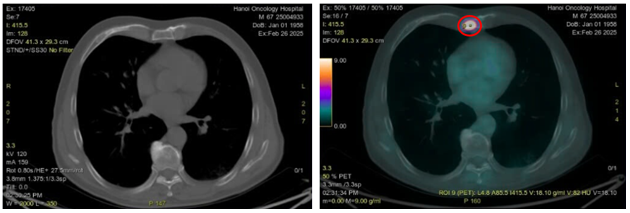

Hình 6: Hình ảnh CT cấu trúc bình thường (bên trái) và hình ảnh tăng hoạt tính phóng xạ ở xương ức trên PET/CT (vòng tròn màu đỏ) (SUVmax: 18,1)